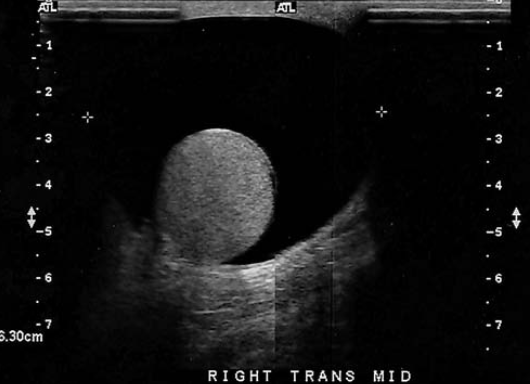

a mass displacing the renal calyces is documented on a recent intravenous pyelogram. A sonogram over this area demonstrates a smooth circular anechoic renal mass. This mass is most sus for

simple cyst